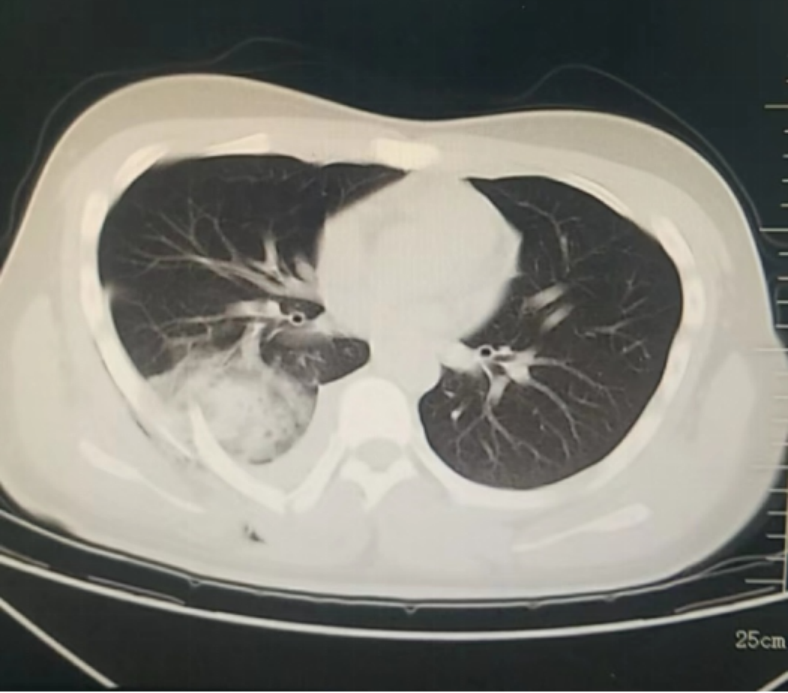

12月26日傍晚,beat365在线唯一官网四院松北院区胸外科医生办公室响起了急促的电话铃声,松北院区急诊科请求紧急会诊一位“特殊”的外伤患者。受伤的小伙子小杨(化名)是一名在校大学生,从小在广州长大,初次来到哈尔滨被冰雪游乐项目吸引,在玩雪圈快速下滑的过程中,不慎背部受到重击,疼痛难忍。医生在电脑上调出电子胶片,不禁心头一惊,患者由于外伤导致右背侧肋骨骨折,恰好有一根断裂的肋骨像“匕首”一样刺入了右肺下叶,出现了严重的血气胸,如果不马上手术,随时可能出现失血性休克,情况十分危急。医院为患者开通绿色通道,救治工作有条不紊地进行。手术非常顺利,仅60分钟左右。在医护人员的护送下,小杨安全地回到了胸外科病房。第二天,小杨已经能够坐起来了,小杨父母紧紧握住医生的手,感激之情难以言表。